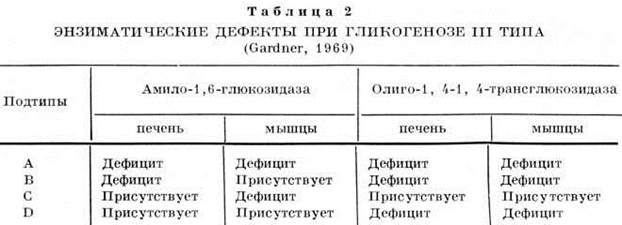

Гликогеноз III типа (болезнь Кори, болезнь Форбса, лемитдекстриноз, debrancher enzyme defect) вызывается полным или частичным отсутствием активности амило-1, 6-глюкозидазы и (или) олиго-1,4-1,4-трансглюкозидазы. Установлено 4 подтипа заболевания (таблица 2). Генетический анализ этого типа Гликогеноз труден из-за наличия нескольких его форм. По клинический, картине относят к мышечной или печеночной форме Гликогеноз

Определение активности амило-1,6-глюкозидазы и олиго-1,4-1,4-траисглюкозидазы в мышцах и печени позволяет установить форму Гликогеноз.